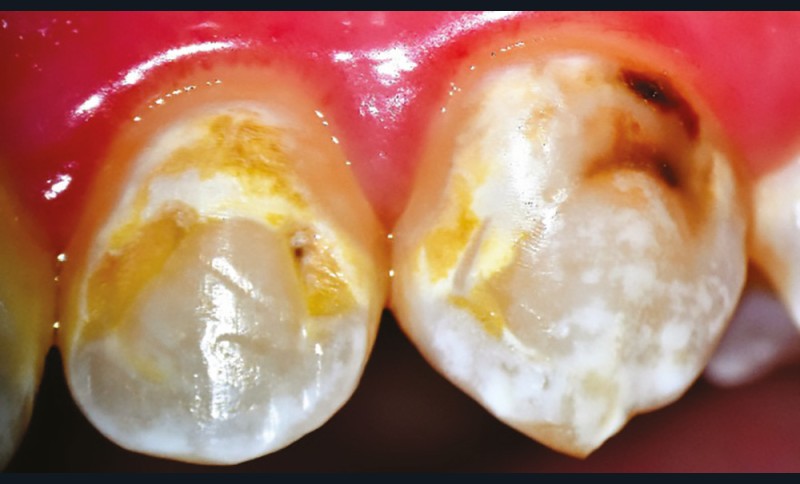

FAUX. Le diagnostic précoce des lésions carieuses se base sur un diagnostic clinique visuel précis à l’aide des classifications visuelles internationales (ICDAS ou ICCMS) et de l’utilisation d’aides optiques (loupes, microscope, caméra avec signal fluorescent ou non) et sur un diagnostic radiographique (à l’aide de deux bitewing, l’un à droite l’autre à gauche) (fig. 1).

• Traitement micro invasif : il s’agit essentiellement de l’érosion/infiltration (fig. 5), mais une alternative peut également être utilisée pour les mêmes indications : le traitement de micro abrasion (fig. 6). L’indication première de cette technique est d’arrêter la progression des lésions carieuses non cavitaires lors d’une déminéralisation de l’émail (ICDAS 2) ou cavitaires au niveau de l’émail sans déminéralisation de la dentine sous-jacente (ICDAS 3) d’un patient à faible risque carieux.